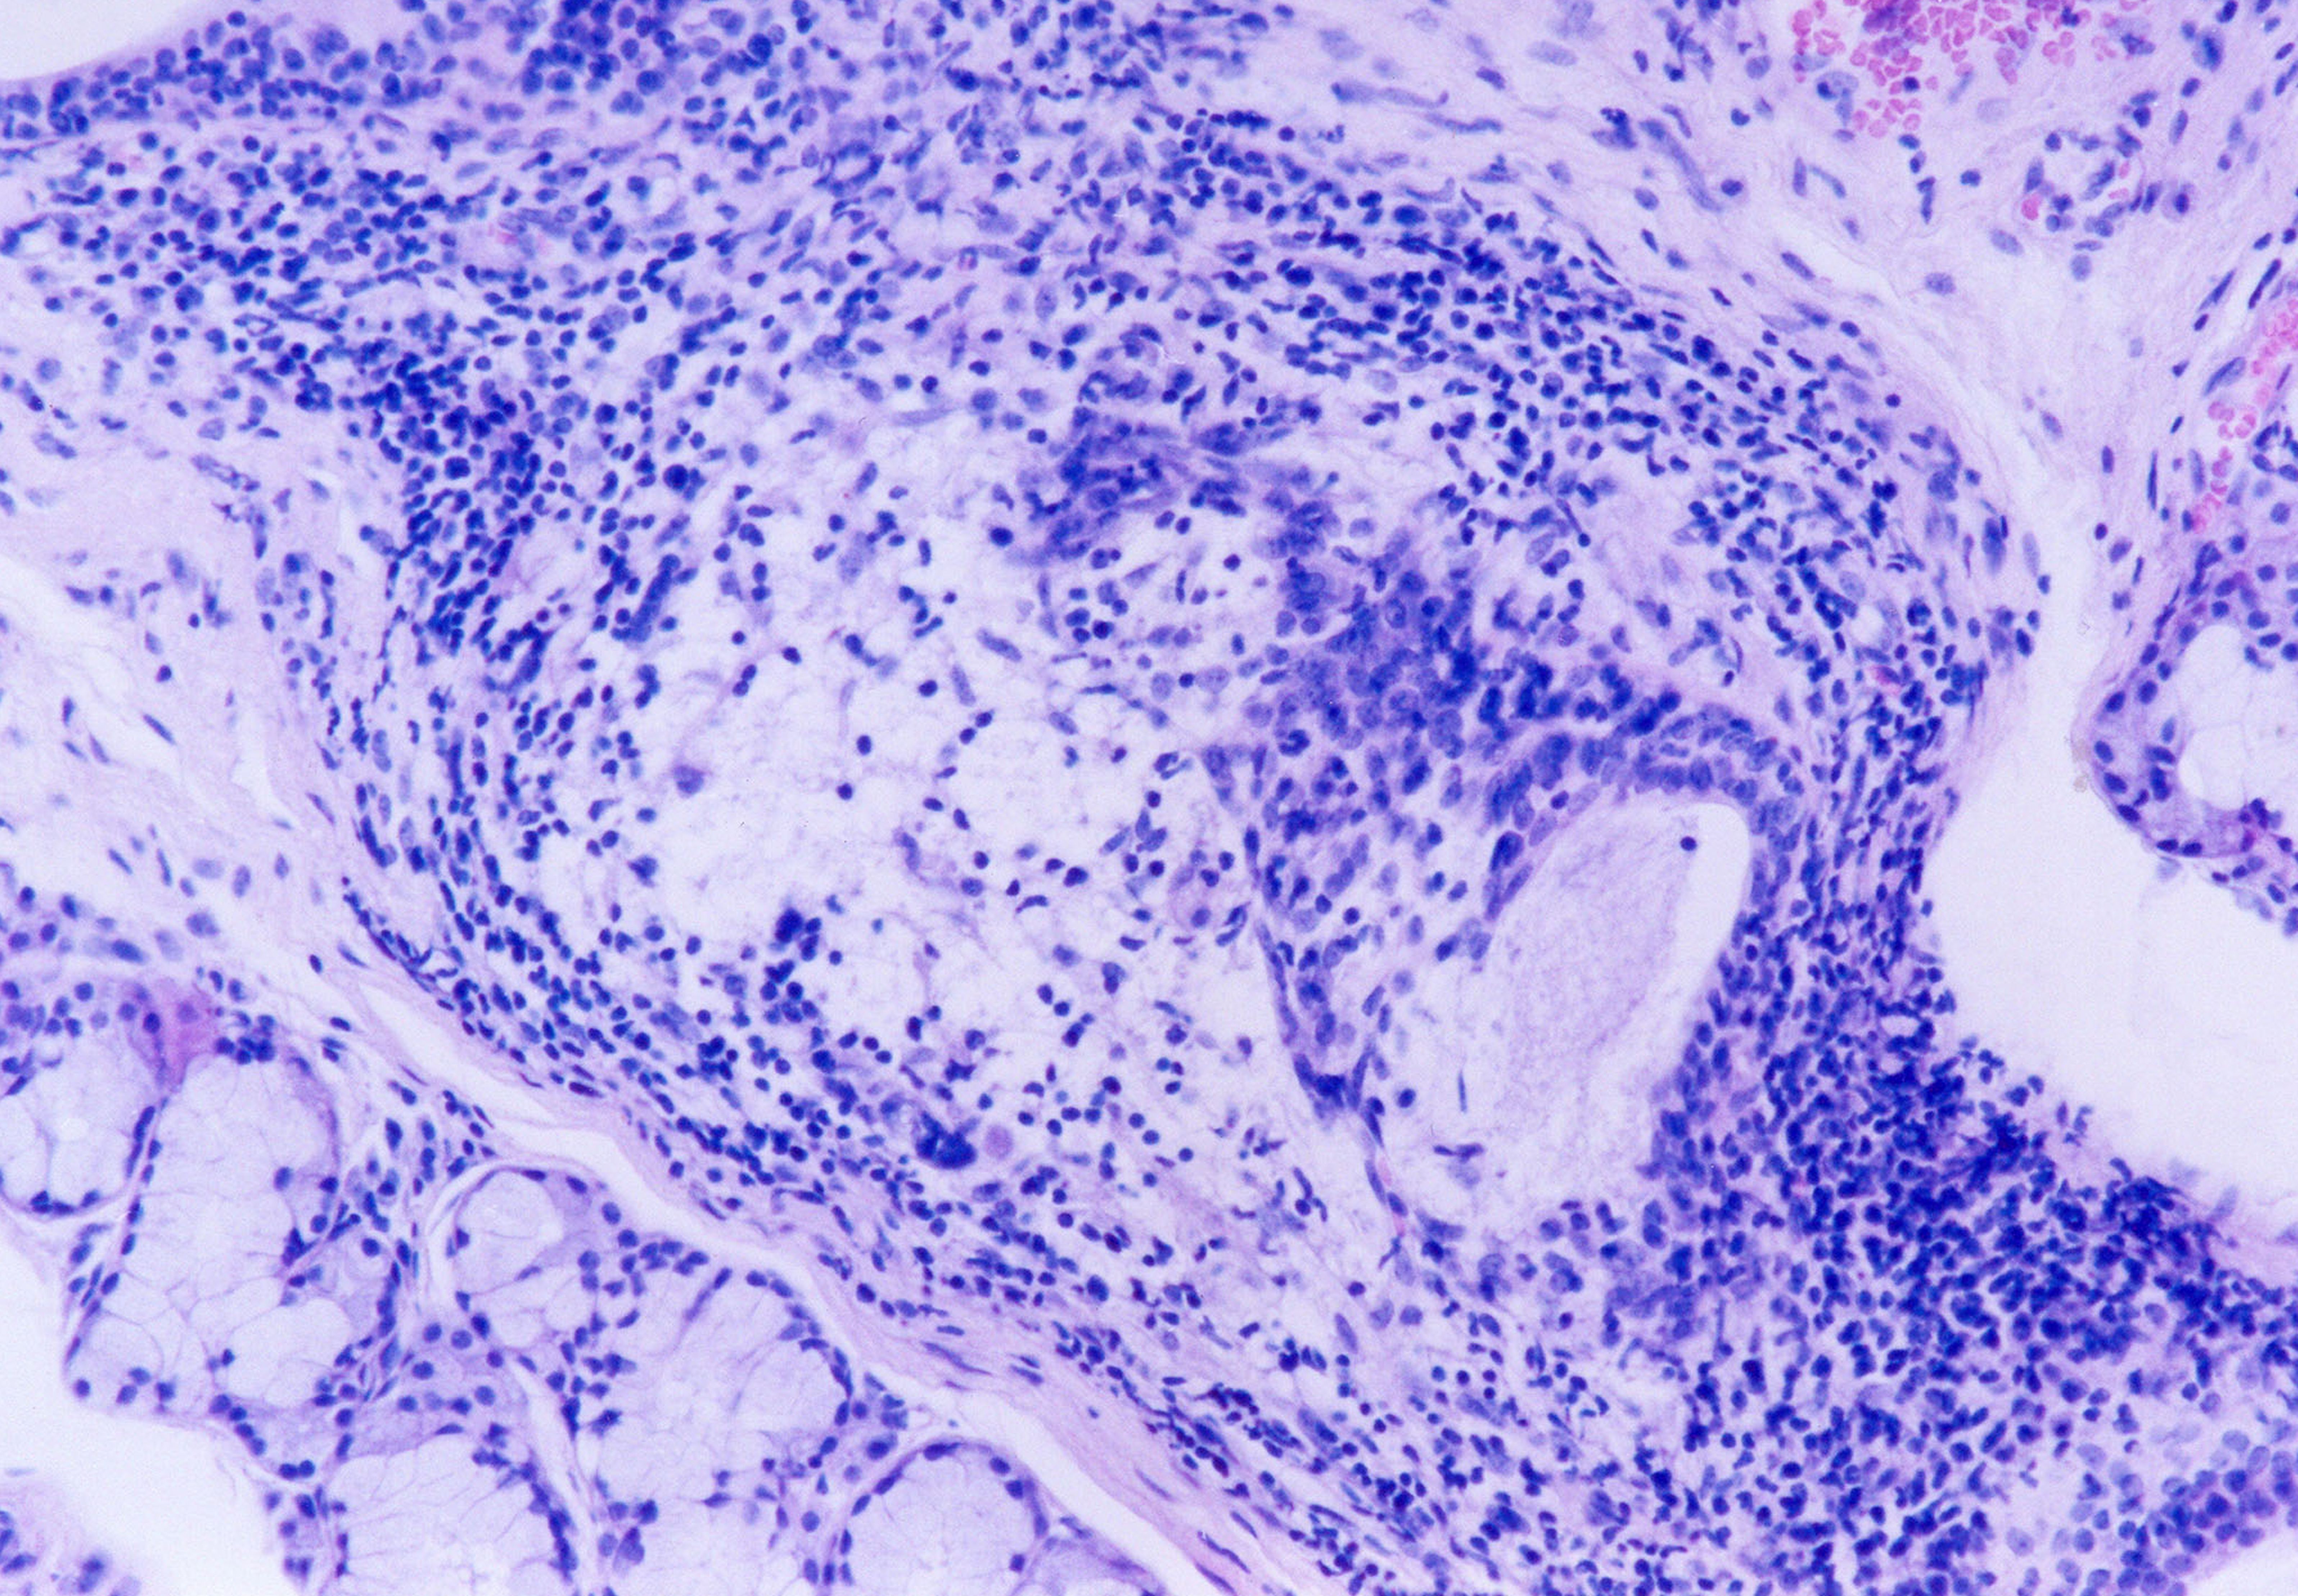

Fig 8. Histopathologic appearance of minor salivary gland biopsy (hematoxylin–eosin). Lower-power magnification showing focal periductal lymphocytic infiltrate (x40).

Figure 8

Fig 9. Histopathologic appearance of minor salivary gland biopsy (hematoxylin–eosin). High-power magnification (x100).

Figure 9

Fig 10. Histopathologic appearance of minor salivary gland biopsy (hematoxylin–eosin). Acinar degeneration (x200).

Figure 10

Fig 11. Histopathologic appearance of minor salivary gland biopsy (hematoxylin–eosin). Proliferation of myoepithelial cells (x400).

Figure 11

The laboratory studies showed hemoglobin, 13.1g/dL; white blood cells, 5140/mm3; and platelets, 165,000/mm3. A serum sample was tested for the presence of antinuclear antibodies (ANA) (indirect immunofluorescence using HEp-2 cell lines), anti-SSA and anti-SSB antibodies (enzyme-linked immunosorbent assay), and rheumatoid factor (nephelometric method). The results demonstrated a dotted pattern for the ANA test (1:320), positive results for anti-SSA test and negative findings for anti-SSB, and the rheumatoid factor was elevated at 80.5 µL/mL (normal, -20). Minor salivary gland biopsy revealed a focal periductal lymphocytic infiltrate, which, taken together with the other diagnostic test findings, confirmed the SS diagnosis (Figure 8 through Figure 11).

The evidence of ocular involvement was obtained using the Schirmer’s test (5 mm in 5 minutes, performed without anesthesia) and was positive for both eyes. Findings from minor salivary gland biopsy revealed a focal periductal lymphocytic infiltrate, which also helped confirm the diagnosis.